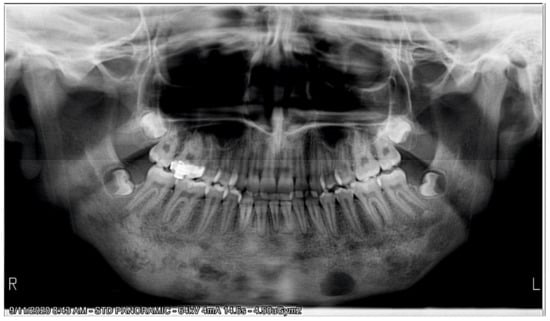

2.1. Initial Diagnosis and Initial Surgical Management

2.3. Treatment Progress

3. Results